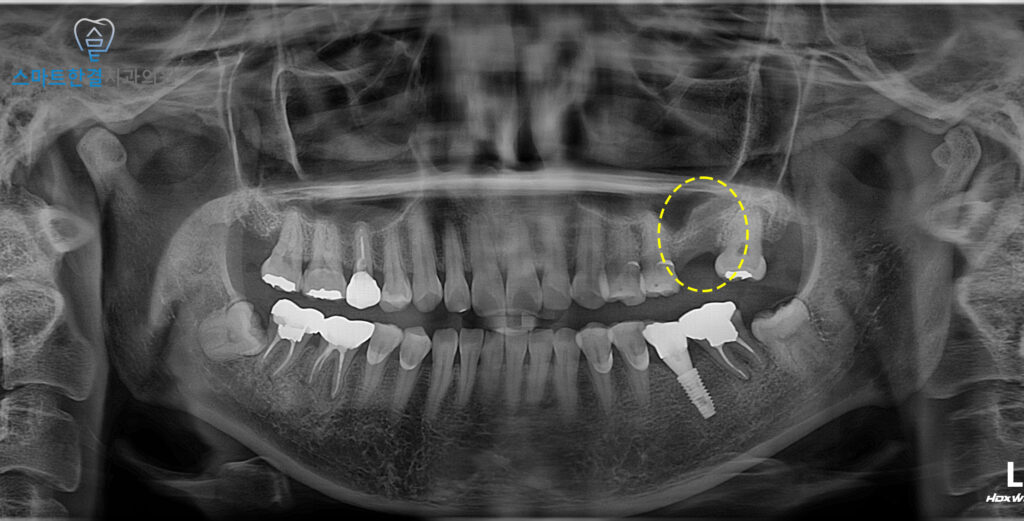

발치 후 파노라마 사진을 촬영하여

염증 부위가 남아 있지 않고

발치와 주변이 깨끗하게 정리된 것을

확인할 수 있었어요.

발치 직후에는 뼈가 차오르기 전까지

치유 과정이 중요한 시기이므로,

정기적인 경과 관찰과 구강 위생 관리가

무엇보다 필요해요!